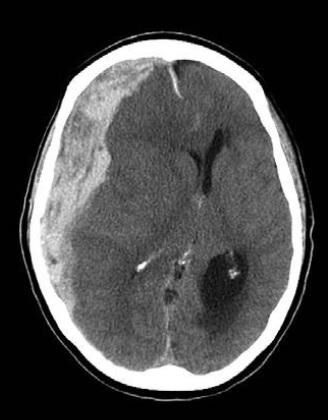

Діагностика

Вдавлений перелом може бути виявлений при хірургічній обробці рани, за допомогою рентгенографії кісток черепа, і краще за все діагностується при виконанні комп’ютерної томографії голови.